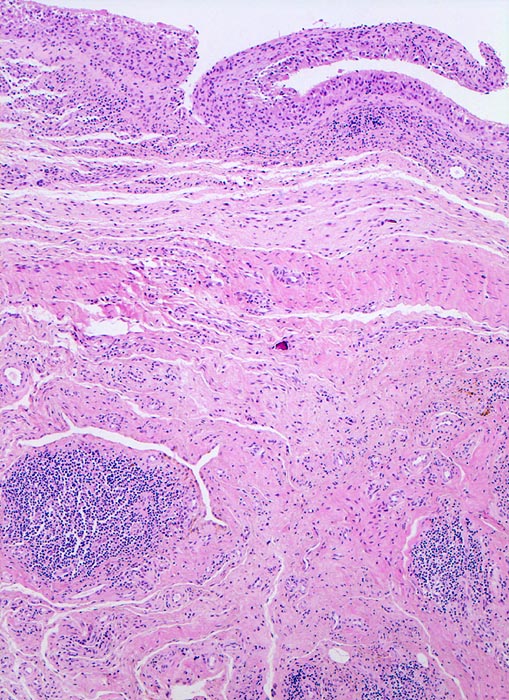

Synovialitis bei chronischer Polyarthritis

Verdickte synoviale Deckzellschicht. Lymphofollikuläre Entzündungsinfiltrate im Stroma.

Bekannte seropositive chronische Polyarthritis.

Der Nachweis von Lymphfollikeln ist typisch, aber nicht beweisend für eine chronische Polyarthritis.